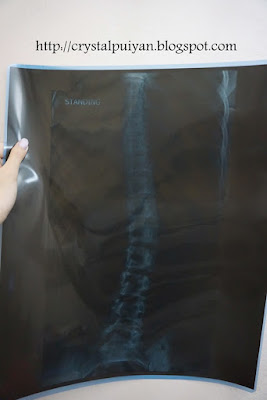

过后就立刻去看医生 然后医生叫我去照x-ray

2012年的时候 ..

结果真的歪了 26度 在他们医科里面要40度以上才算严重

严重的定义就是要开刀动手术 不知该喜该悲 我不上不下 不能开刀

重点来了 有一天心血来潮 我就叫妈妈带我去照x-ray

三年了 当然要看看自己穿了那双鞋那么久 有没有什么improvement

2015...

DANG DANG! 感觉奇迹出现了 从26度变到20度

整整直了6度! 或许6度对你来说就是很少 可是对我来说 已经是很大的进步了

2012 VS 2015 (这样看比较看得出分别吧)